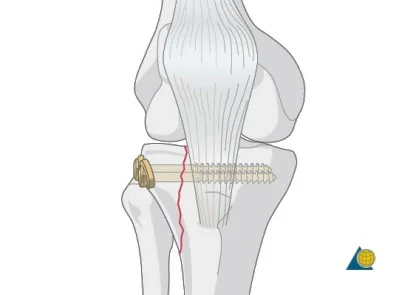

| Tension Band Wires | Special mechanics in – Patella – Olecranon – Malleolar fractures | ![]() |